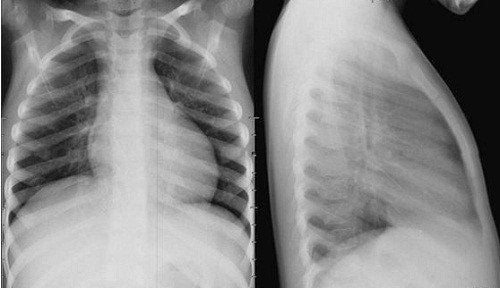

2.1 Chụp X-quang phổi

Kết quả chụp X-quang phổi có thể giúp phát hiện khối u nhưng lại ít khi thấy được các tổn thương nhỏ khác trong phổi. Chụp X-quang để xét nghiệm ung thư phổi được chia thành 2 loại, bao gồm:

• Chụp X-quang phổi: Đây là phương pháp được dùng để tìm kiếm các khối u ở phổi. Tuy nhiên, phương pháp này không hiệu quả khi tìm kiếm các tổn thương nhỏ đi kèm.

Chụp X quang phổi đánh giá căn bệnh ung thư phổi